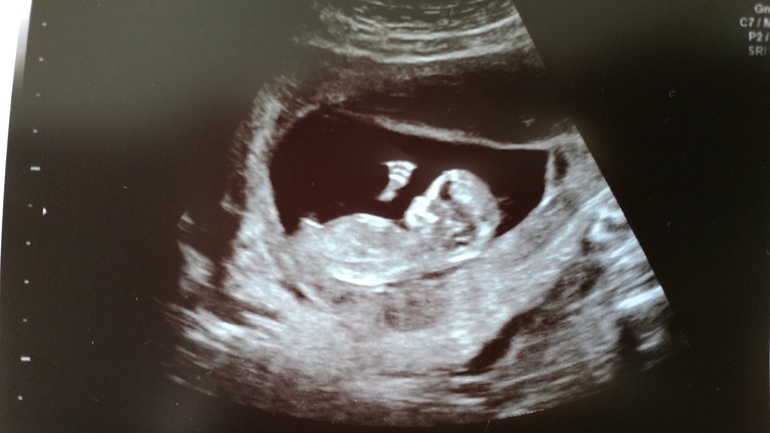

Первый скриннинг

Всё о нашей беременностиСегодня нам 12,4 недели и был первый скриннинг. 3 недели не видела малышей и так соскучилась за ними. Слёзы счастья сами непроизвольно текли по щекам. У малышей там была целая дискотека. Махали маме ручкой. У нас всё тьфу тьфу тьфу хорошо, а меня пока беспокоит только токсикоз

14.07.2017